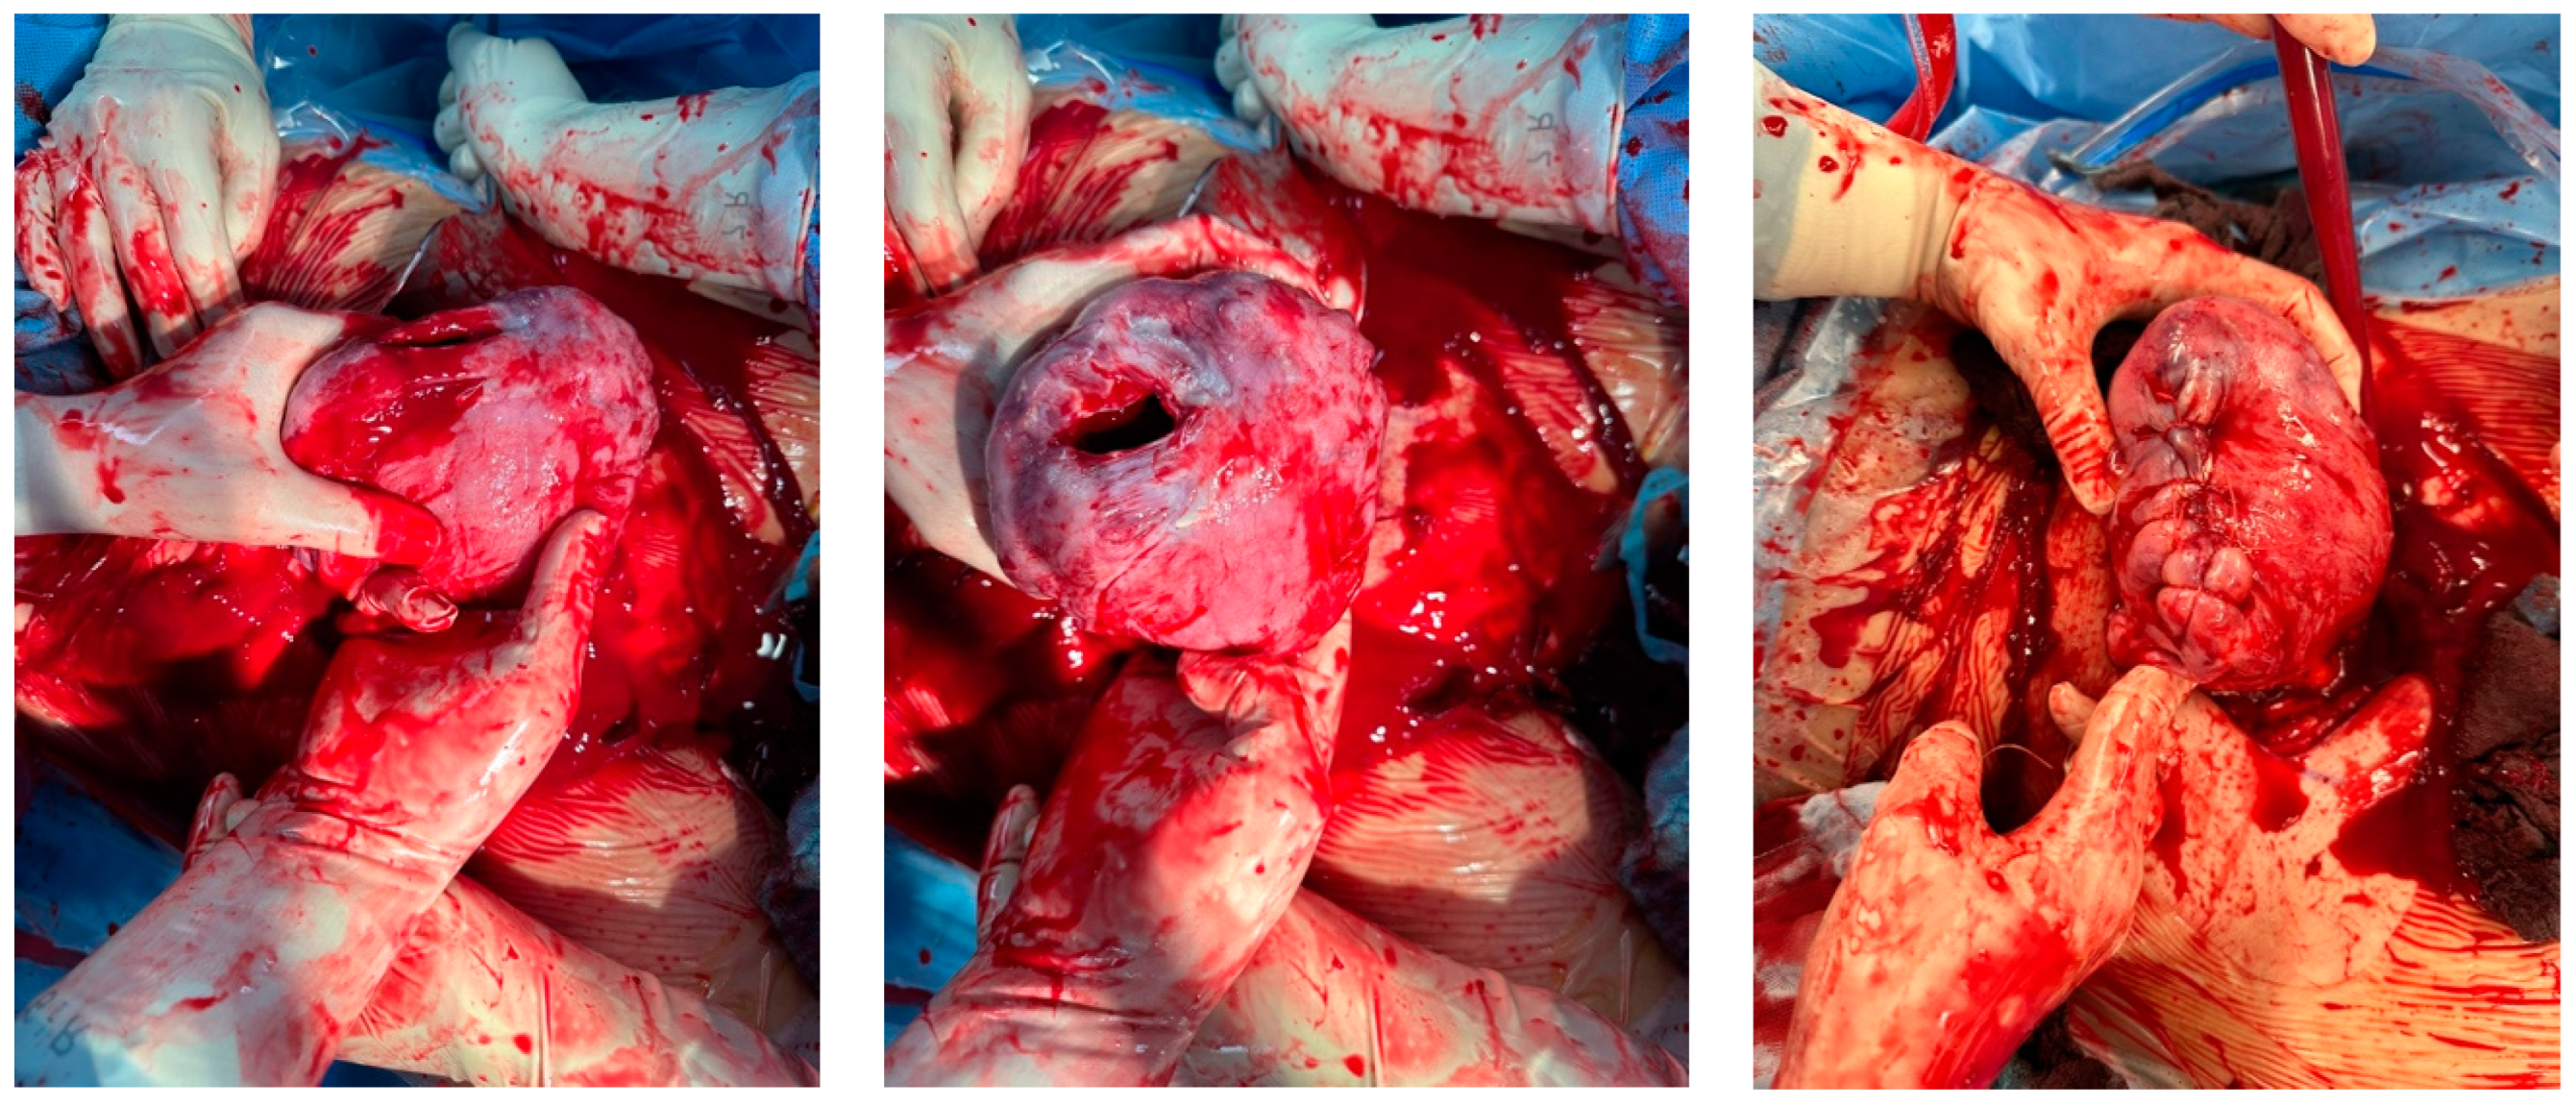

Intraoperative findings (Figure 8):

Figure 8.

Depict the uterus during and after hysterectomy performed for placenta increta.

Histological findings of the uterus weighing 939 g revealed the following:

- Parts of a placenta increta located close to the sutured ruptured area.

- Absence of decidua basalis in the affected area, with focal necroses visible.

- The rest of the serosa showed no additional pathological findings.